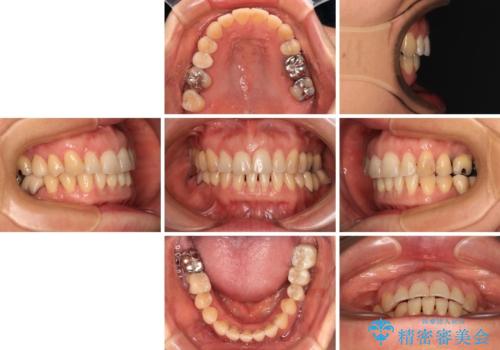

正中のズレと飛び出した前歯を改善 メタルブラケットでの抜歯矯正

- 飛び出した上顎前歯と正中のズレを気にして来院された患者様です。

上顎正中が右側にずれていたので、むし歯が酷く抜歯が必要な左側臼歯を抜歯して正中を改善することとしました。

左下には新しいセラミックのブリッジが装着されていたため、ブリッジを壊さずに改善できるところまで咬み合わせを改善していくこととしました。

右上小臼歯は銀歯が装着されており、ワイヤー矯正の装置が装着できないため、事前に仮歯に変えてから矯正治療を行い、その後オールセラミッククラウンにて補綴治療を行いました。